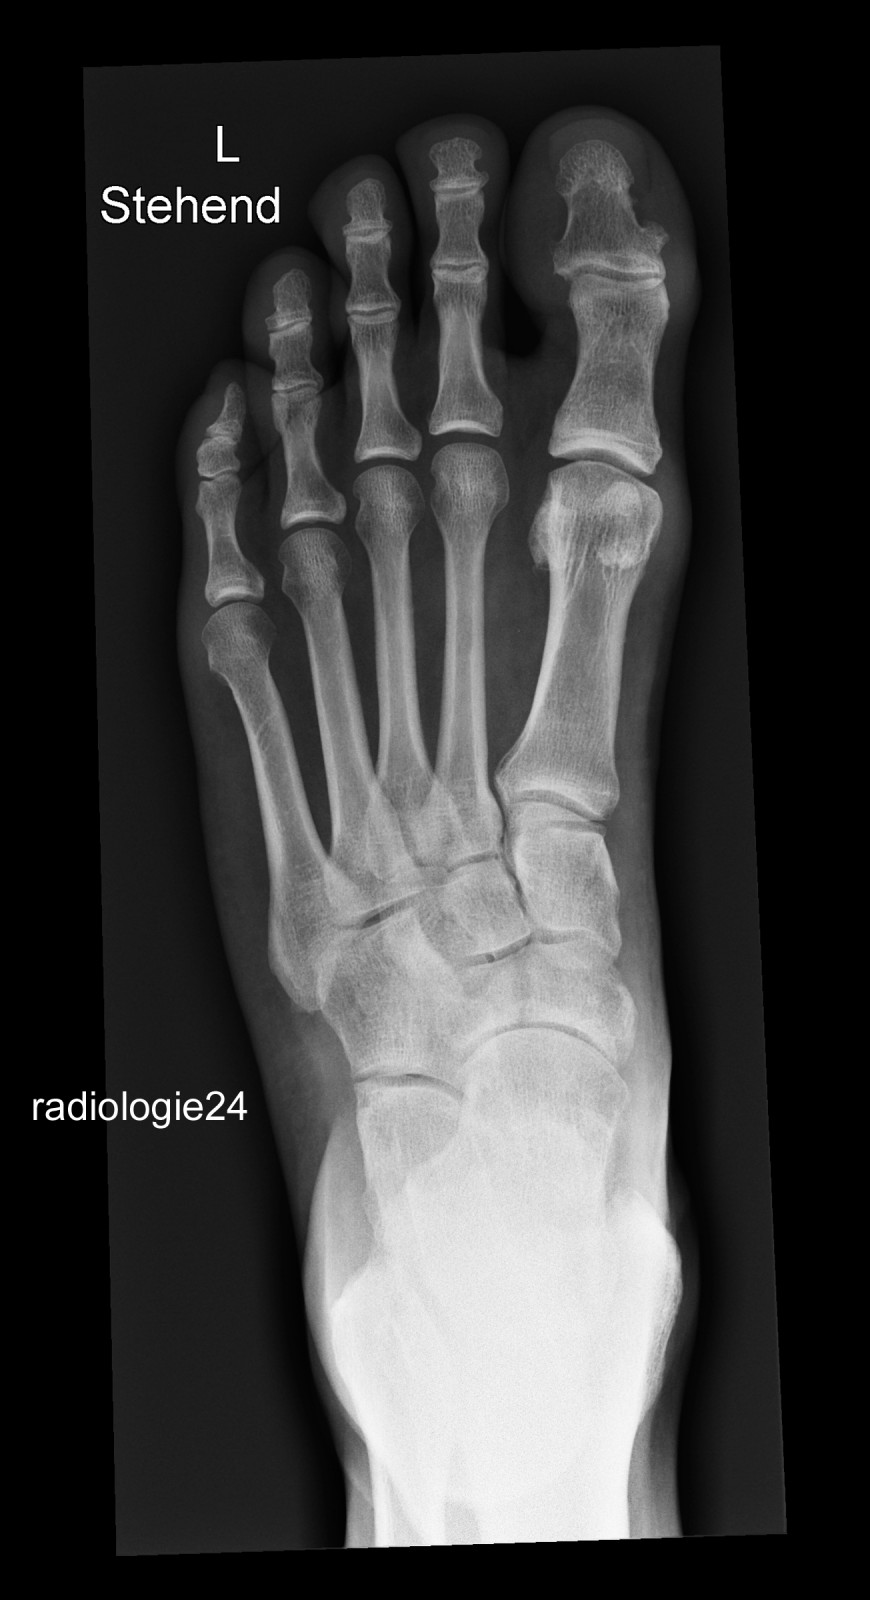

Röntgenfall des Monats September 2018 mit Auflösung

52 jähriger Patient

Fehltritt beim Wandern. Schmerzen Mittelfuss.

Ihre Diagnose? Weitere radiologische Diagnostik notwendig?